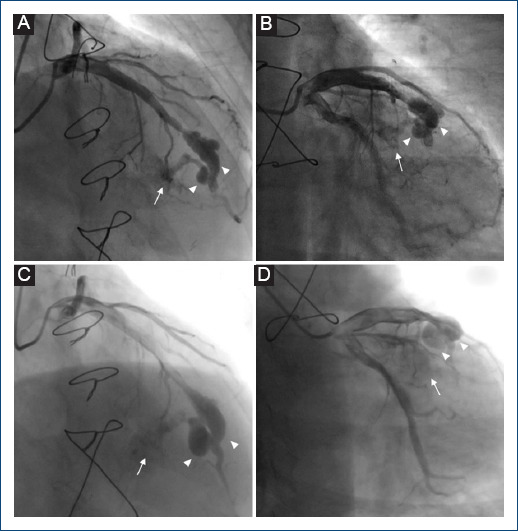

[Aneurysms and coronary artery fistula after endomyocardial biopsy in a patient with a heart transplant. Angiographic and clinical evolution. Report of a case.]

{"title":"[Aneurysms and coronary artery fistula after endomyocardial biopsy in a patient with a heart transplant. Angiographic and clinical evolution. Report of a case.]","authors":"Pedro D Díaz-Sarasa, Herón G Méndez-Sánchez, Guering Eid-Lidt","doi":"10.24875/ACM.24000036","DOIUrl":null,"url":null,"abstract":"","PeriodicalId":93885,"journal":{"name":"Archivos de cardiologia de Mexico","volume":" ","pages":"111-114"},"PeriodicalIF":0.0000,"publicationDate":"2024-07-09","publicationTypes":"Journal Article","fieldsOfStudy":null,"isOpenAccess":false,"openAccessPdf":"https://www.ncbi.nlm.nih.gov/pmc/articles/PMC12148514/pdf/","citationCount":"0","resultStr":null,"platform":"Semanticscholar","paperid":null,"PeriodicalName":"Archivos de cardiologia de Mexico","FirstCategoryId":"1085","ListUrlMain":"https://doi.org/10.24875/ACM.24000036","RegionNum":0,"RegionCategory":null,"ArticlePicture":[],"TitleCN":null,"AbstractTextCN":null,"PMCID":null,"EPubDate":"","PubModel":"","JCR":"","JCRName":"","Score":null,"Total":0}